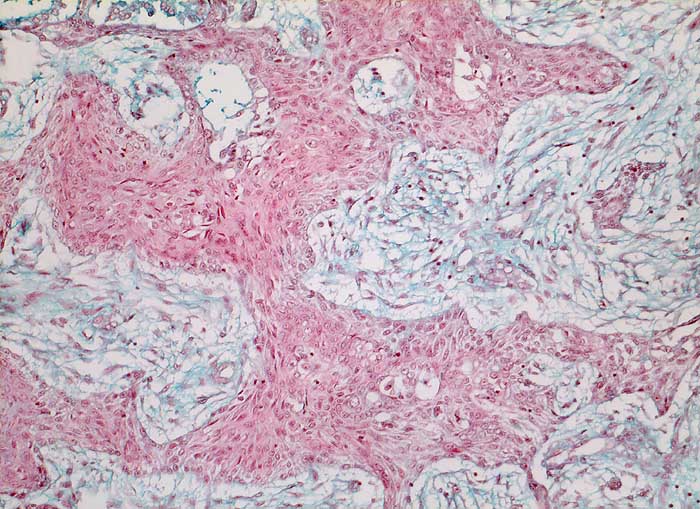

Die häufigeren nicht verhornenden Plattenepithelkarzinome bilden eher Verbände. Die Tumorzellen sind uniformer, das dichte Zytoplasma ist blau-grün gefärbt und scharf begrenzt. Die Zellkerne sind hyperchromatisch und enthalten grosse Nukleolen. Die Abgrenzung des nicht verhornenden Plattenpithelkarzinoms vom Adenokarzinom kann schwierig sein. In der Regel ist das Kernchromatin der Plattenepithelkarzinome dichter und die Nukleolen weniger prominent.

Die Abbildungen zeigen ein verhorntes und ein unverhorntes Plattenepithelkarzinom zum Vergleich.